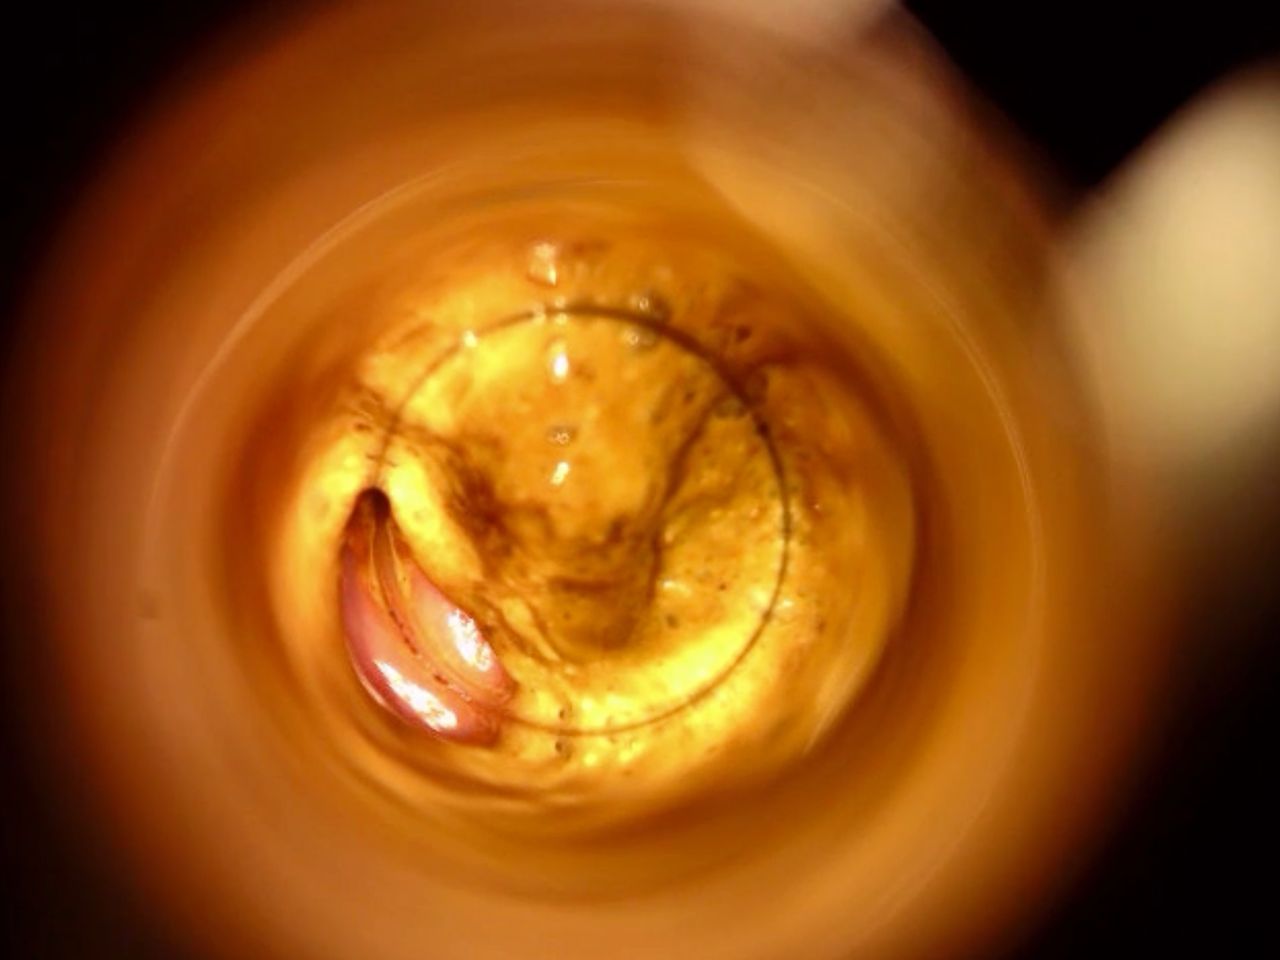

La cura delle emorroidi patologiche, finalmente senza dolore

Come Chirurgo Vascolare, sono perfezionata in Proctologia da molti anni, e molti altri ne ho passati direttamente in sala operatoria, praticando l'emorroidectomia con metodo Milligan-Morgan.

Durante la mia esperienza come Chirurgo Protcologo, ho visto personalmente come i trattamenti chirurgici disponibili, benché necessari, fossero comunque abbastanza invasivi per il paziente, specialmente nel decorso post operatorio.

Fortunatamente, negli ultimi anni sono stati messi a punto protocolli non chirurgici molto avanzati, che ho personalmente studiato ed approfondito con molto interesse.

Tra questi, ho cominciato ad utilizzare il trattamento sclerotizzante con scleromousse stabilizzata ad aria sterilizzata, che considero ormai il 'Gold Standard' per il trattamento non invasivo e permanente delle emorroidi patologiche.

Ho quindi attrezzato il mio studio con il moderno Videoproctoscopio Digitale, nonché con avanzate pompe miscelatrici ad aria sterilizzata, in grado di ottenere una scleromousse stabilizzata di grande qualità, perfetta per il trattamento emorroidale.

Grazie a questo protocollo, posso risolvere casi anche molto gravi di prolasso emorroidale, garantendo una risoluzione definitiva in oltre il 95% dei casi clinici.

Il tutto, senza il minimo dolore o disagio per il paziente.